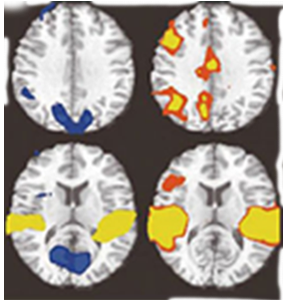

마음챙김 초보자(일반인)

휴식중

마음챙김중

마음챙김 수행자

1968년, 마음챙김의 효과를 과학적으로 검증하기 위한 연구가 8주간의 수련을 통해 진행되었으며, 그 결과 대뇌피질 좌측 전두엽의 활성 증가가 확인되었습니다. 연구에서는 스트레스로 인한 교감신경계의 과잉 활성은 완화되고, 안정 상태를 조절하는 부교감신경계의 기능이 상대적으로 우세해지는 변화가 관찰되었습니다. 특히, 마음챙김 수행자의 전두엽 활성 수준은 일반인보다 높게 나타났습니다. 이러한 연구 결과를 바탕으로, 1975년 하버드 의과대학에서는 일반인을 대상으로 한 마음챙김 치료법 「이완반응」을 도입하였습니다.